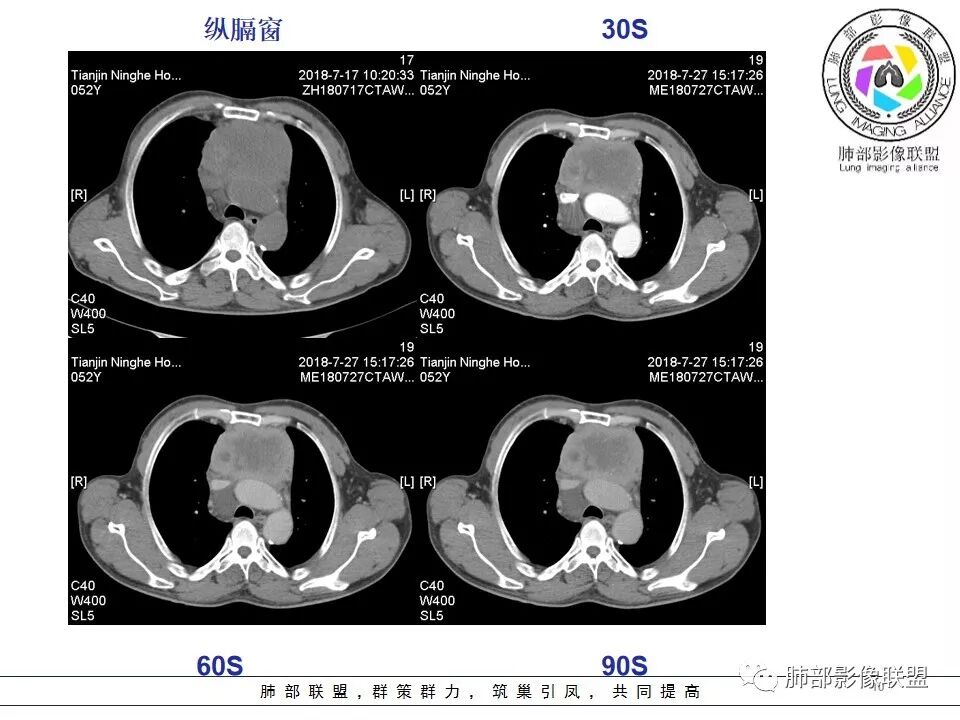

我们分析一下影像.

较大,内有囊变、钙化。

南边:边界大部分清楚,有些地方毛糙。

附近有淋巴结

上腔静脉如何?

心包如何?

南边:强化就不用说了

大肿块,边缘不清,伴随肿大淋巴结,上腔静脉受侵犯——恶性

侵袭性胸腺瘤?胸腺癌?老年,钙化、肿大淋巴结,边缘侵犯、累及心包、侵犯上腔静脉——支持

4.  纵隔淋巴结肿大及纵隔大血管(上腔静脉)受侵犯,提示胸腺癌或类癌。

结合临床表现患者应该存在左无名静脉明显侵犯,可惜未提供相应层面影像资料。

5. 此患者NSE增高,提示神经内分泌肿瘤可能,纵隔神经内分泌癌最常见的是不典型类癌,胸腺类癌临床上可伴相关临床表现。肿瘤体积巨大,边缘清晰,强化显著(与鳞癌不同),肿瘤内边缘规则的管状血管影(鳞癌内血管是破坏、纤细、僵硬);